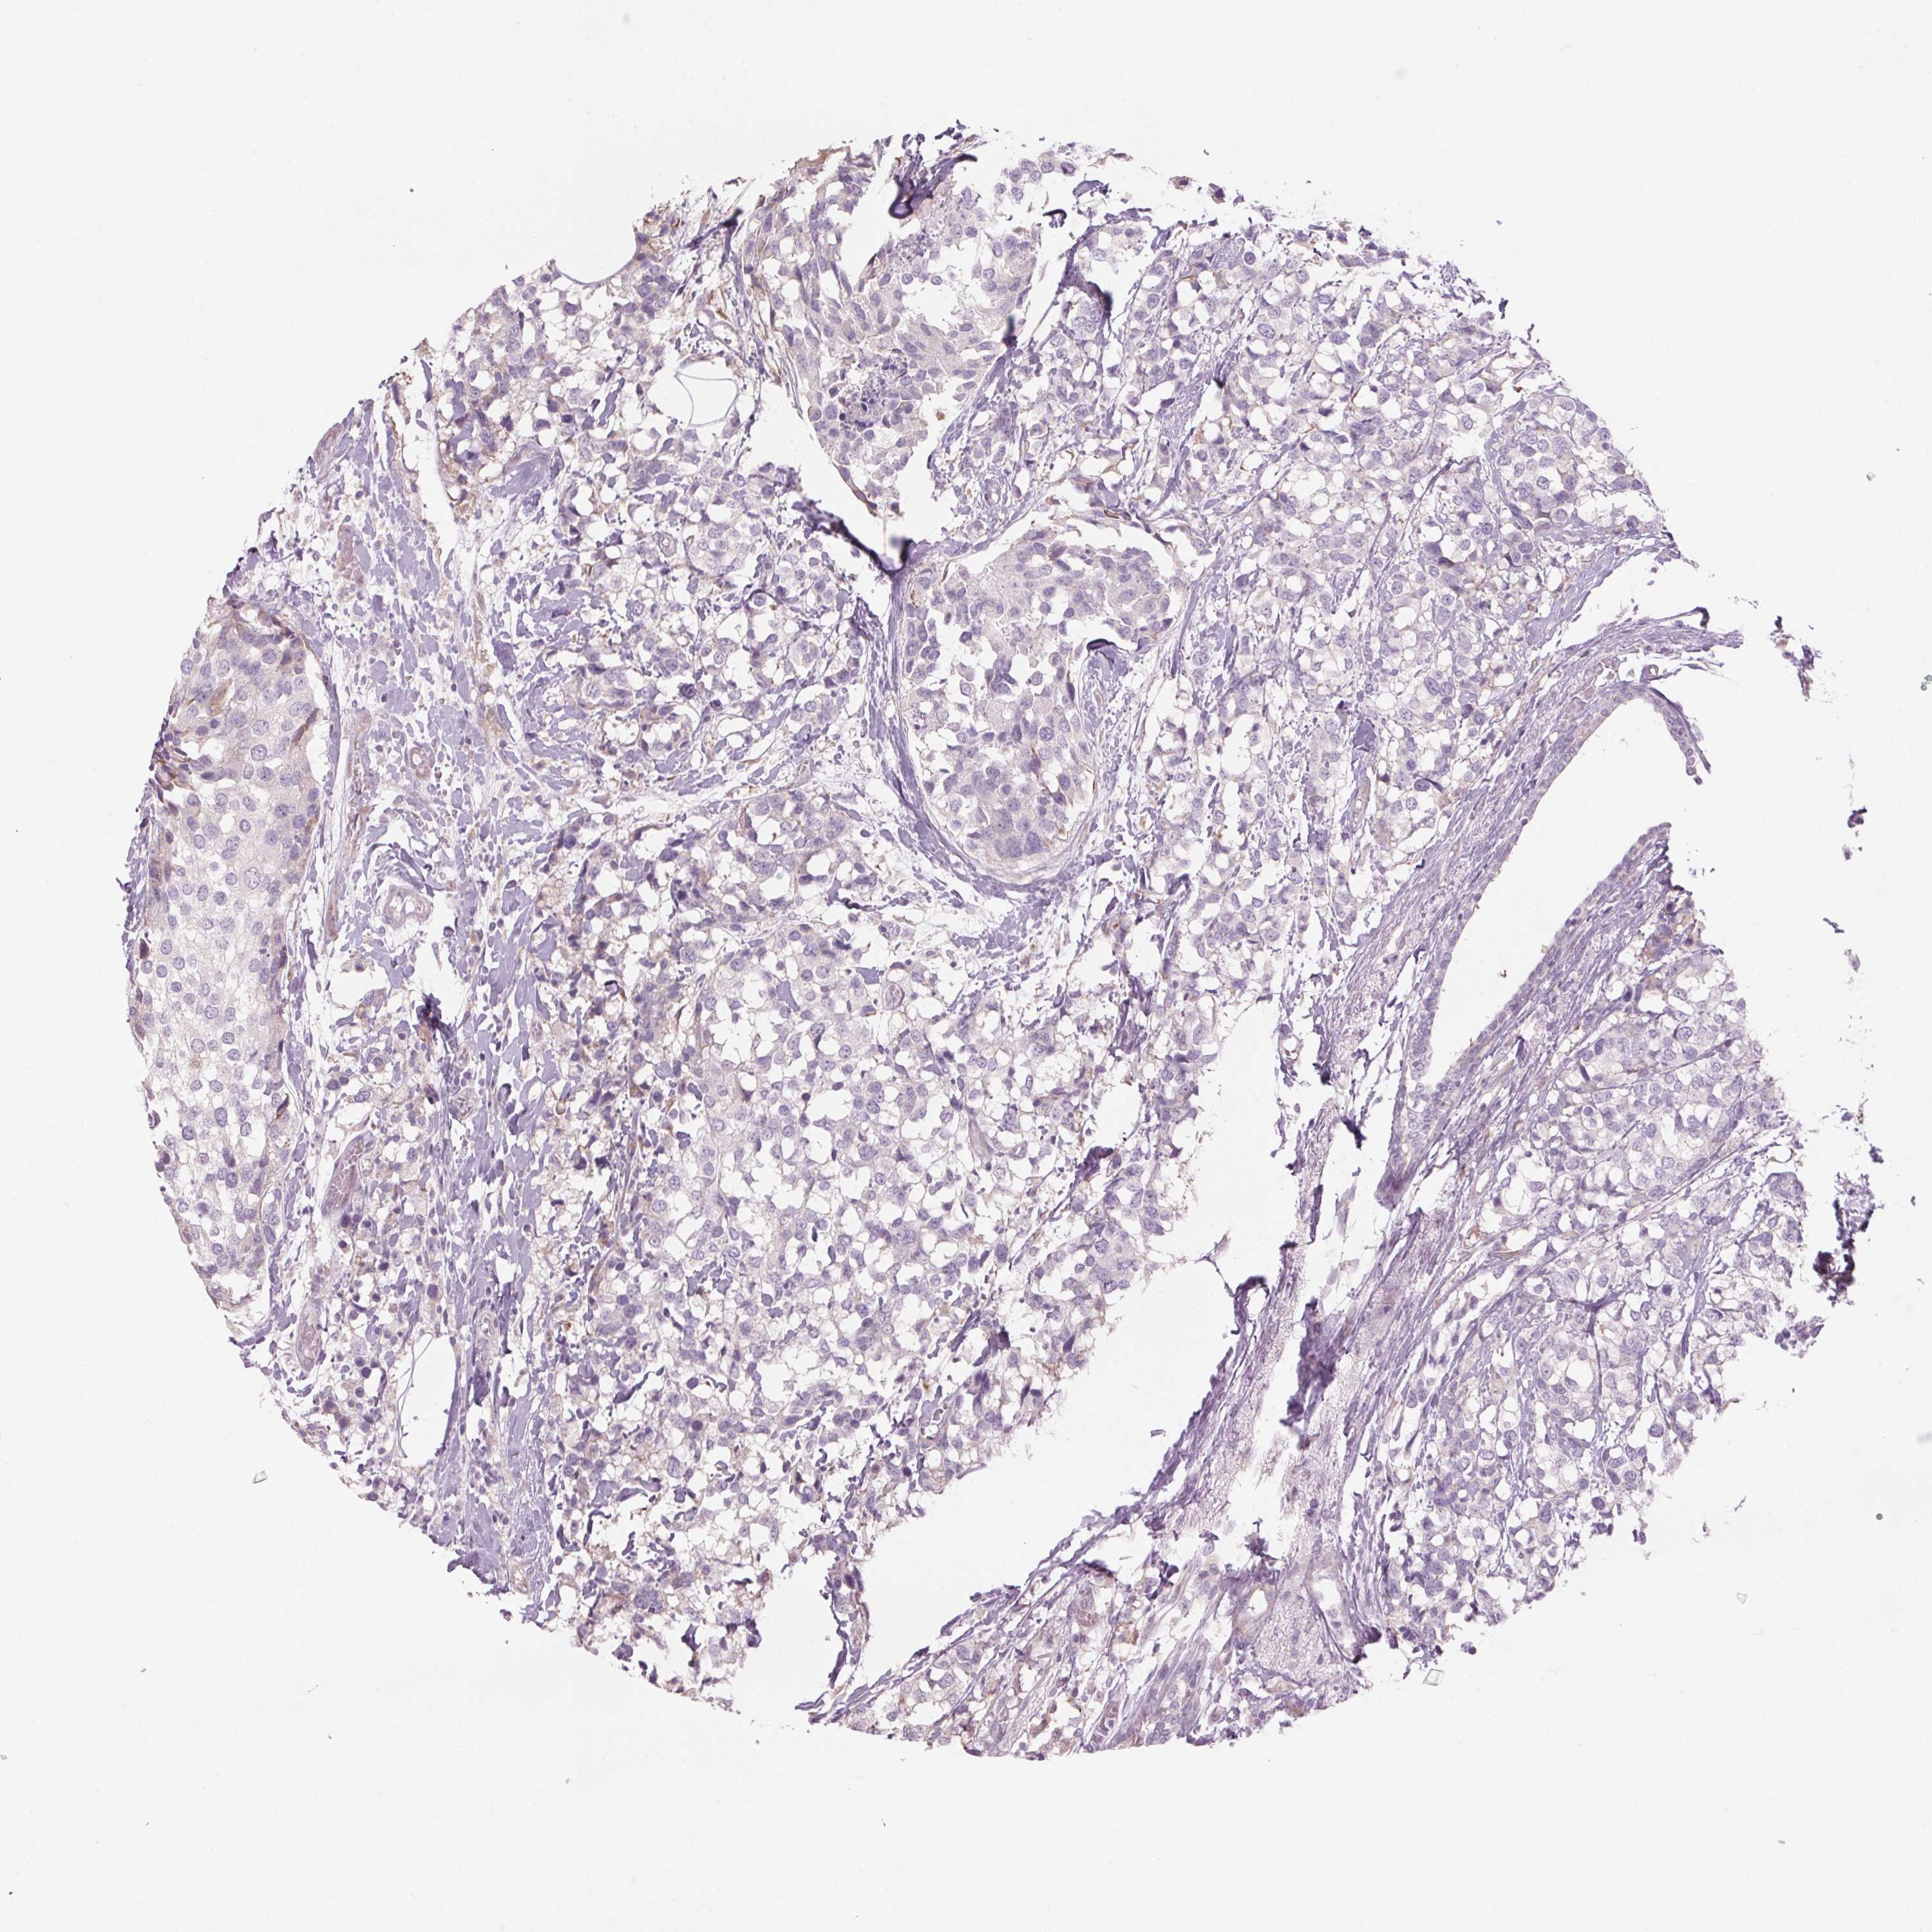

CANCER BREAST CANCER Show tissue menu

BRCA TCGA BRCA VALIDATION PROTEIN EXPRESSION

ANTIBODIES

AND

VALIDATION